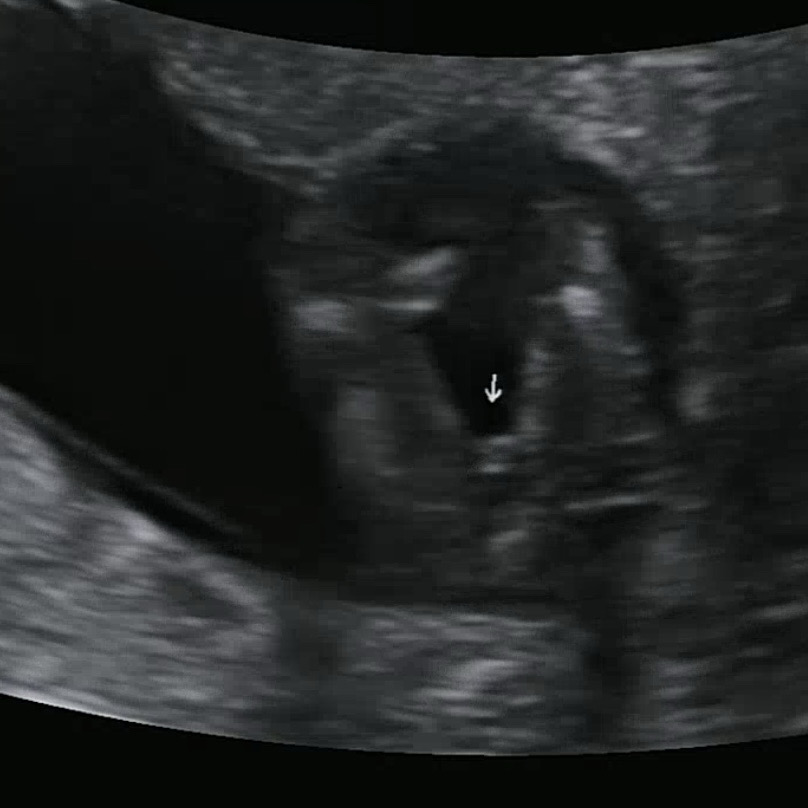

13주5일이에요!! 이정도면 딸 맞겠죠???????? 선생님은 거의 확실하다고 하시는데 괜히 반전될까봐 무섭네용 ㅠ

ㅎㅎ딸일거같아요~ 저는 같은시기에 거의 아들확정받았는데 뭔가 확실하게 있어요! 🤣🤣

13주정도면 딸일거같아요! 이때쯤 아들이라면 확실히 뭐가 보이긴할거같아서ㅎㅎㅎ